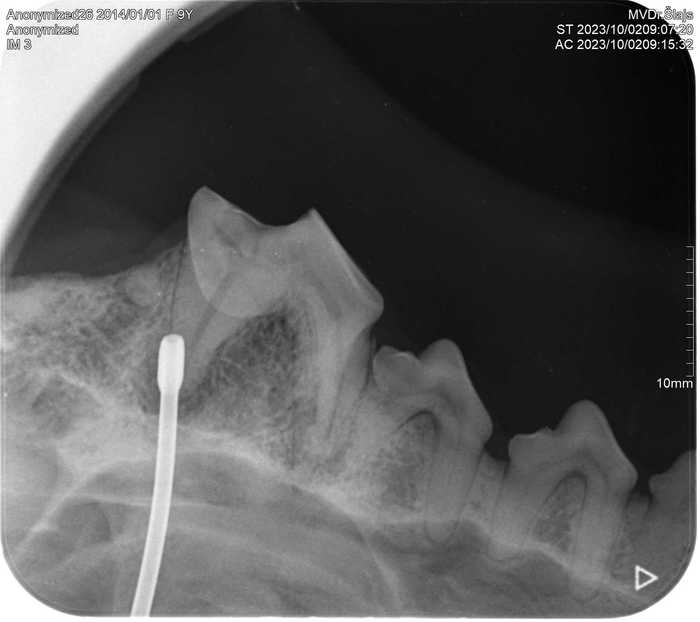

Již nyní má na našem pracovišti RTG vyšetření nezastupitelné místo během vyšetření zubů a dutiny ústní u králíků, morčat, psů i koček.

Zubní intraorální RTG nám umožňuje přesnější diagnostiku onemocnění zubů, díky čemuž je úspěšnější i léčba.

S pomocí intraorálního RTG s vysokým rozlišením jsme schopni ještě před vlastním zubařským zákrokem přesně stanovit diagnózu a rozhodnout, zda a kde přesně provést chirurgický zákrok.

Díky posouzení zubních kořenů a stavu kostního podkladu zubů můžeme provést zákrok přesně v místě, kde je potřeba a stanovit následnou léčbu tak, aby hojení probíhalo co nejrychleji a pacient nemusel zbytečně podstupovat opakované ošetření.